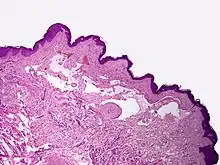

Microscopically, the vesicles in lymphangioma circumscriptum are greatly dilated lymph channels that cause the papillary dermis to expand. They may be associated with acanthosis and hyperkeratosis. There are many channels in the upper dermis which often extend to the subcutis (the deeper layer of the dermis, containing mostly fat and connective tissue). The deeper vessels have large calibers with thick walls which contain smooth muscle. The lumen is filled with lymphatic fluid, but often contains red blood cells, lymphocytes, macrophages, and neutrophils. The channels are lined with flat endothelial cells. The interstitium has many lymphoid cells and shows evidence of fibroplasia (the formation of fibrous tissue). Nodules (A small mass of tissue or aggregation of cells) in cavernous lymphangioma are large, irregular channels in the reticular dermis and subcutaneous tissue that are lined by a single layer of endothelial cells. Also an incomplete layer of smooth muscle also lines the walls of these channels. The stroma consists of loose connective tissue with a lot of inflammatory cells. These tumors usually penetrate muscle. Cystic hygroma is indistinguishable from cavernous lymphangiomas on histology.[4]